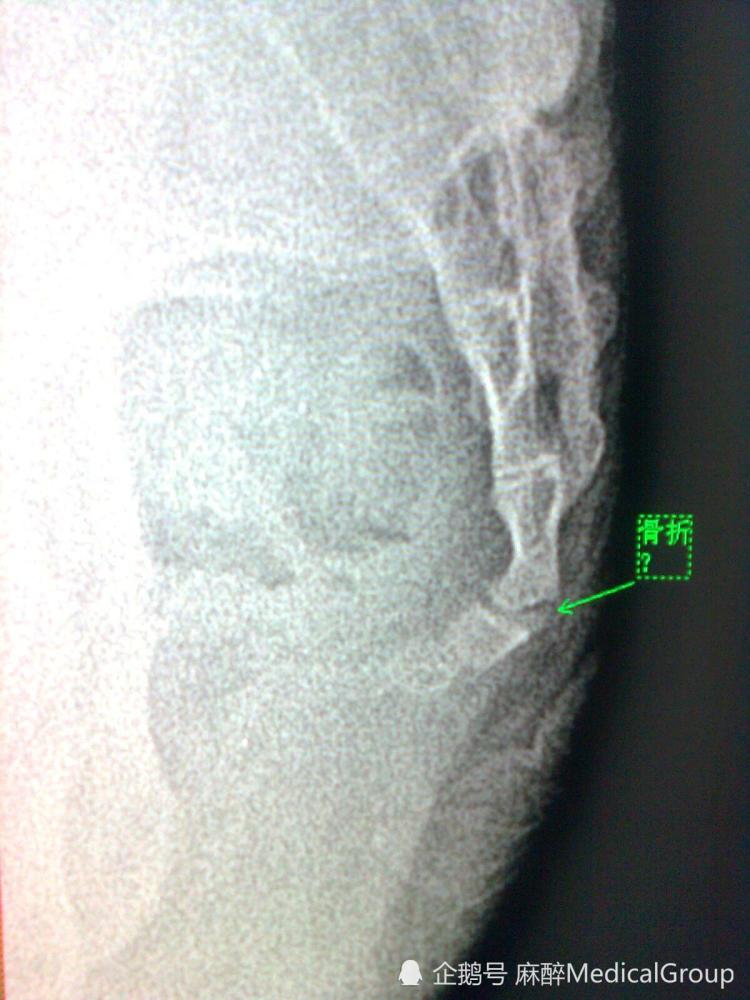

尾椎骨,骨折与否

图片尺寸780x1040